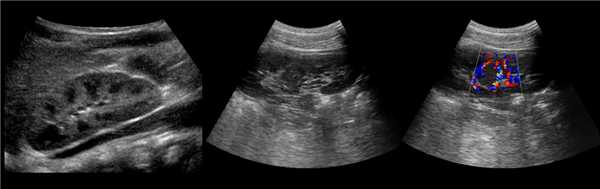

• Серошкальное УЗИ:

о Гомогенное округлое образование, изоэхогенное корковому веществу почки

о Расположена между почечными пирамидами

о Нормальные контуры почки

о Ограничена гиперэхогенной линией соединительной паренхимы и гиперэхогенным треугольным дефектом соединительной паренхимы

о Вдается в почечную пазуху с латеральной стороны

о Гиперэхогенность может быть обусловлена анизотропией

• Цветовая допплерография:

о Нормальная перфузия указывает на неизмененную почечную ткань

о Отсутствует деформация сосудов с нормальными дугообразными артериями, окружающими пирамиды

о Отсутствуют аномальные сосуды

(Левый) На рисунке показана бертиниева колонна, которая является не истинным новообразованием, а разрастанием коркового вещества почки между пирамидами.

(Правый) На продольном ультразвуковом срезе правой почки визуализируется гипертрофированная колонна Бертена, вдающаяся в клетчатку почечной пазухи в среднем отделе почки. Обратите внимание на ее изоэхогенность корковому веществу и гладкие наружные контуры.